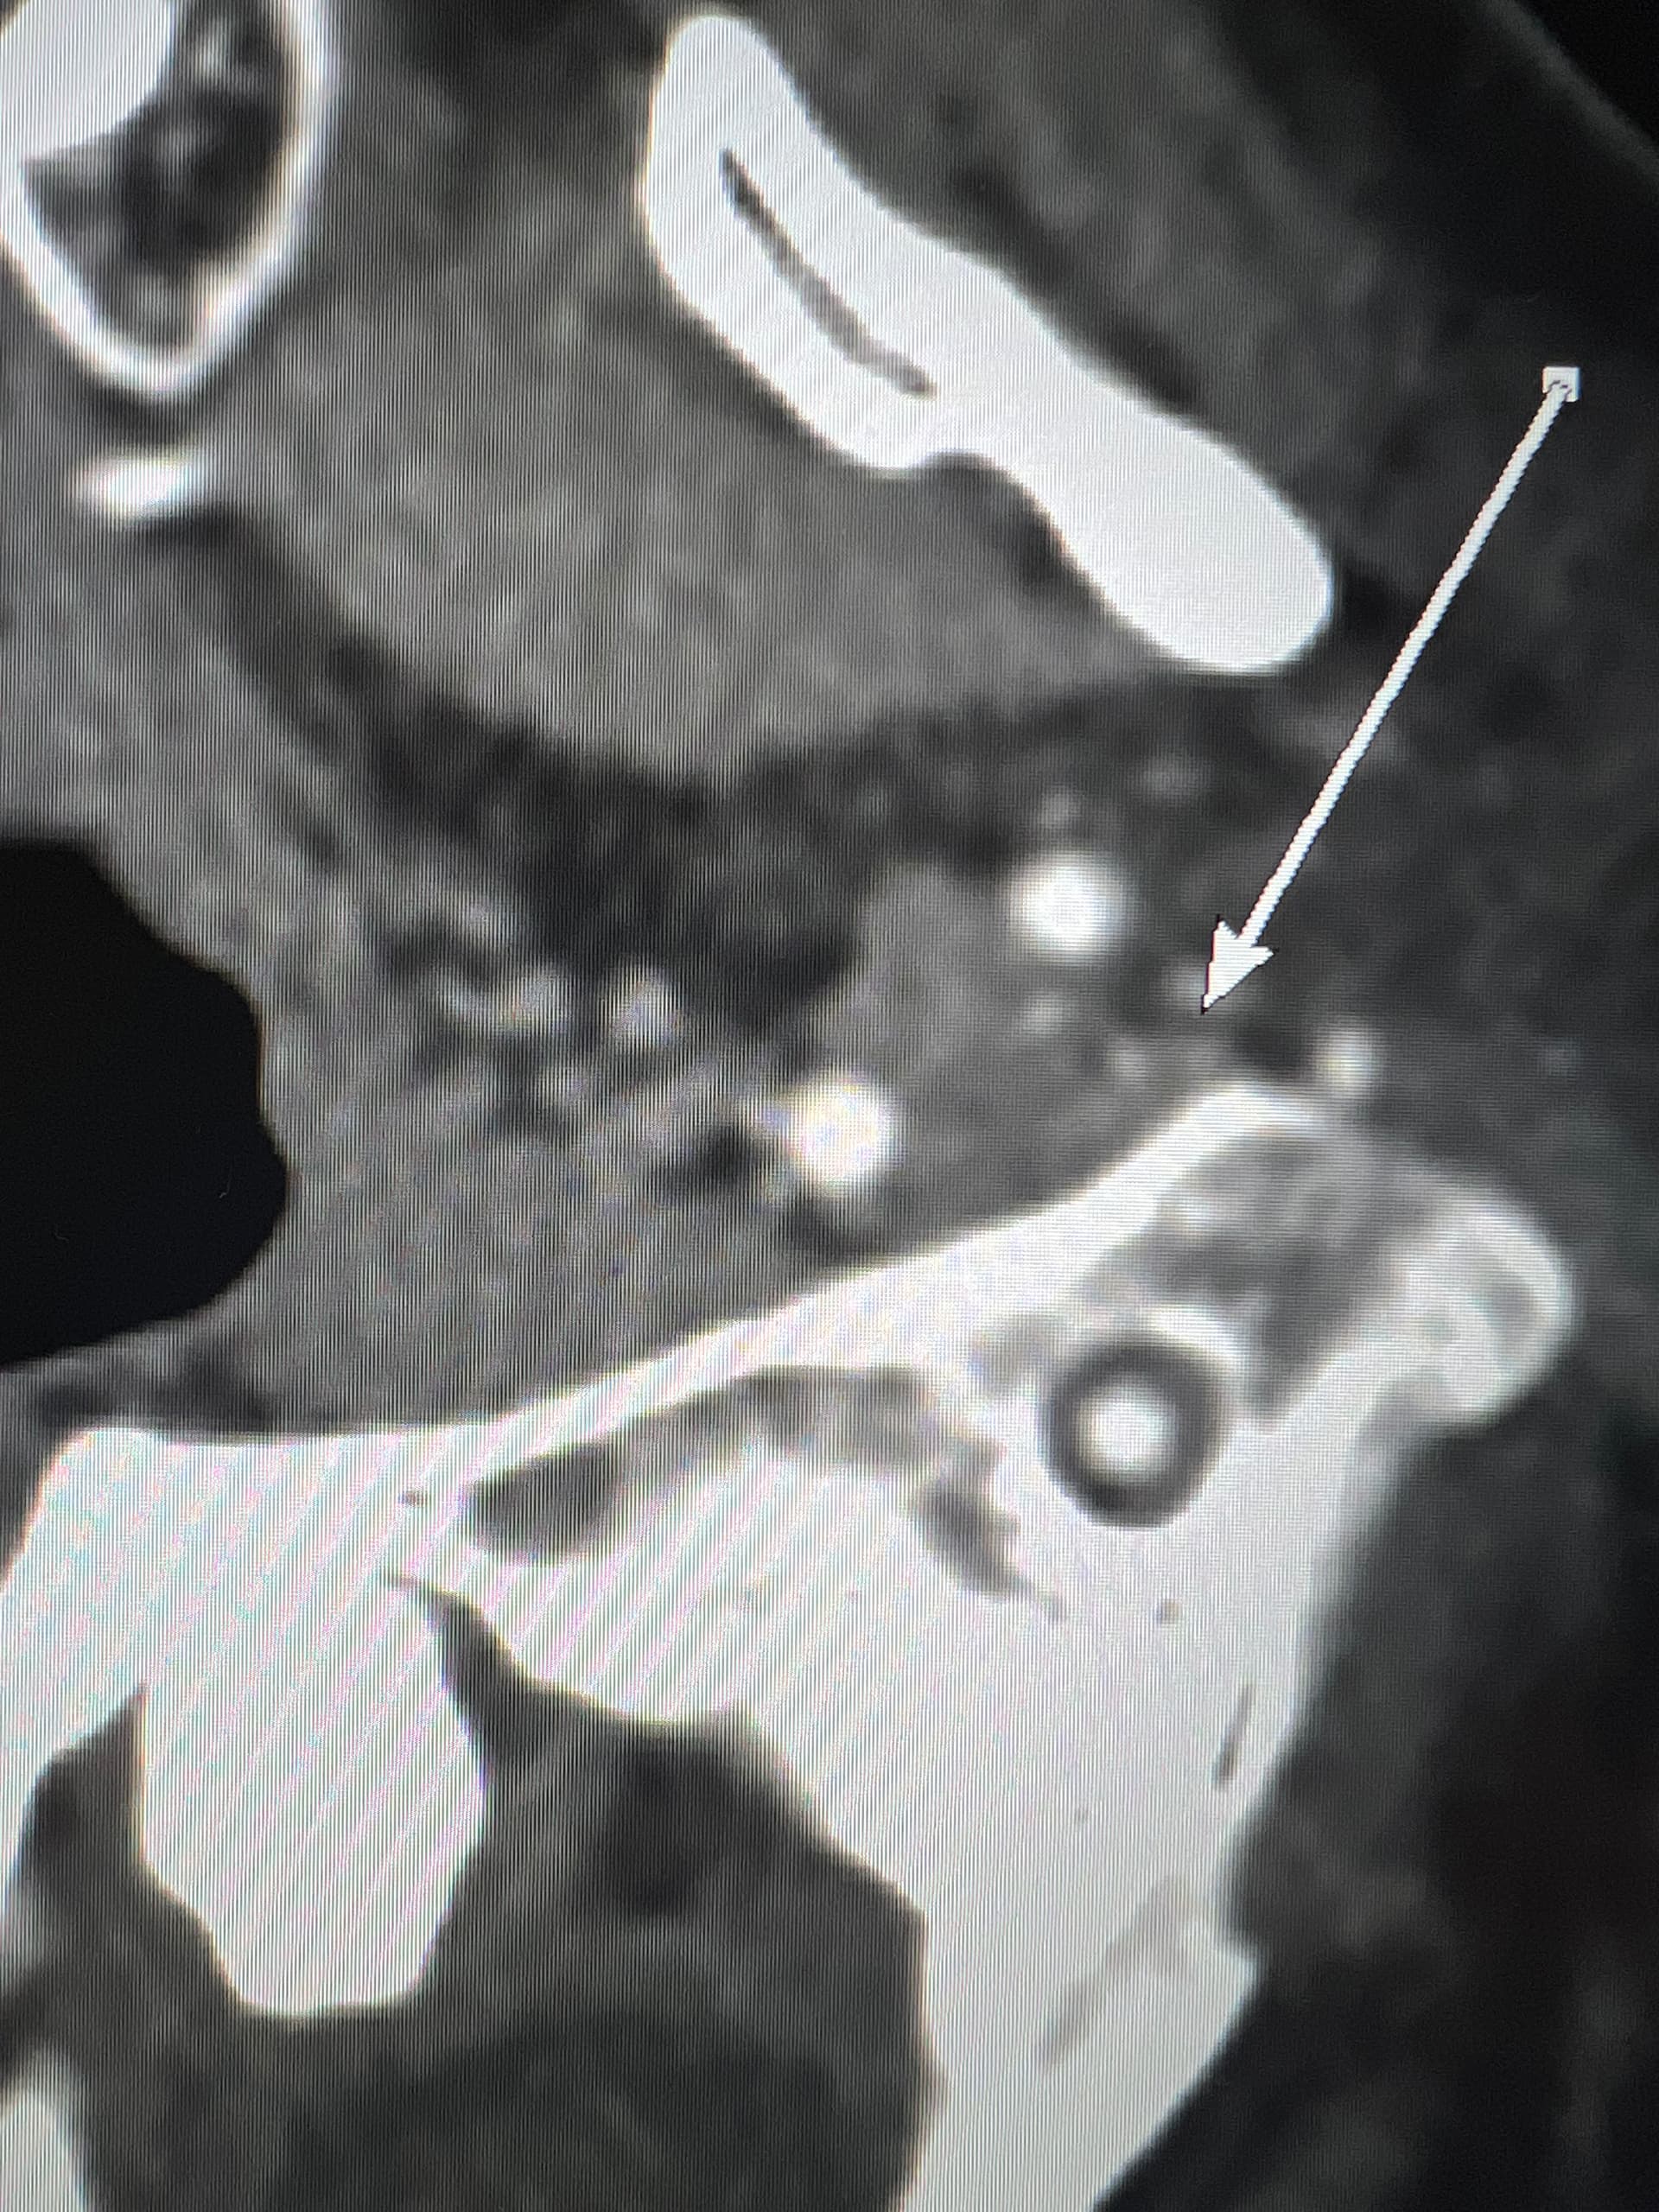

I’ve uploaded some photos. Some are repetitive but I know some in this group are skilled in reading these.

I also added some 3D photos. My left JV looks extremely narrow at around C3. Does anyone else see that?

@Luckee7 - I’ve marked some vascular structures that are above & beneath your C1 vertebra that I haven’t seen before in other imaging so am not sure what they are or if they could be involved in causing symptoms. Those above C1 appear to be “sitting” on it which appears to be causing some minor compression of those sections. They could be collateral veins, & if so, then they’re likely contributing to skull base/occipital pain.